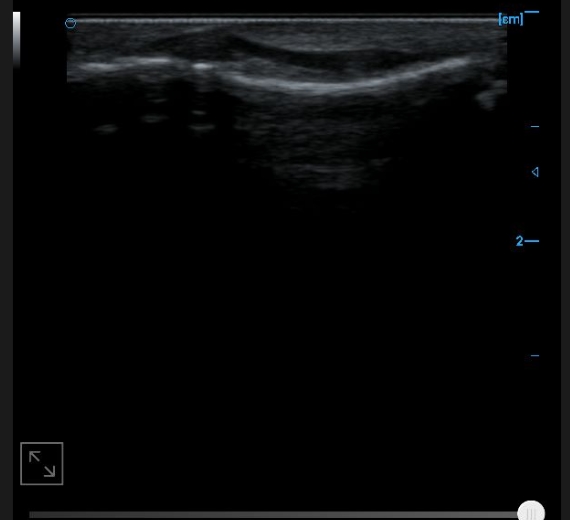

B-image of femoral trochlear cartilage